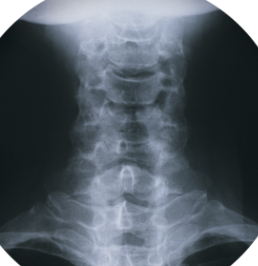

목 디스크 증상 원인 치료방법 알아봐요.목 디스크는 목의 디스크가 손상되거나 변형되어 인접한 신경을 압박하는 질환입니다. 이로 인해 목 부분에서 통증, 근육 약화, 저림현상 등의 증상이 나타나며, 심한 경우 두통, 어지러움 등의 증상도 나타날 수 있습니다. 주로 중년 이후 발생하며, 노화와 함께 진행되는 질환입니다. 목 디스크의 원인으로는 나이, 유전, 외상, 잘못된 자세, 비만 등이 있으며, 치료 방법으로는 치료 운동, 물리치료, 침술, 약물 치료, 수술 등이 있습니다.

목 디스크는 목의 디스크가 손상되거나 변형되어 인접한 신경을 압박하는 질환으로, 다음과 같은 증상을 보일 수 있습니다.